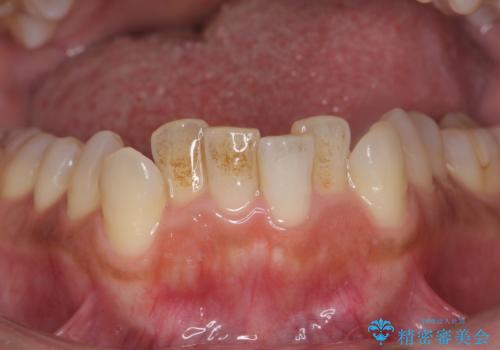

セラミックを付ける前にエアフローで綺麗ににクリーニング